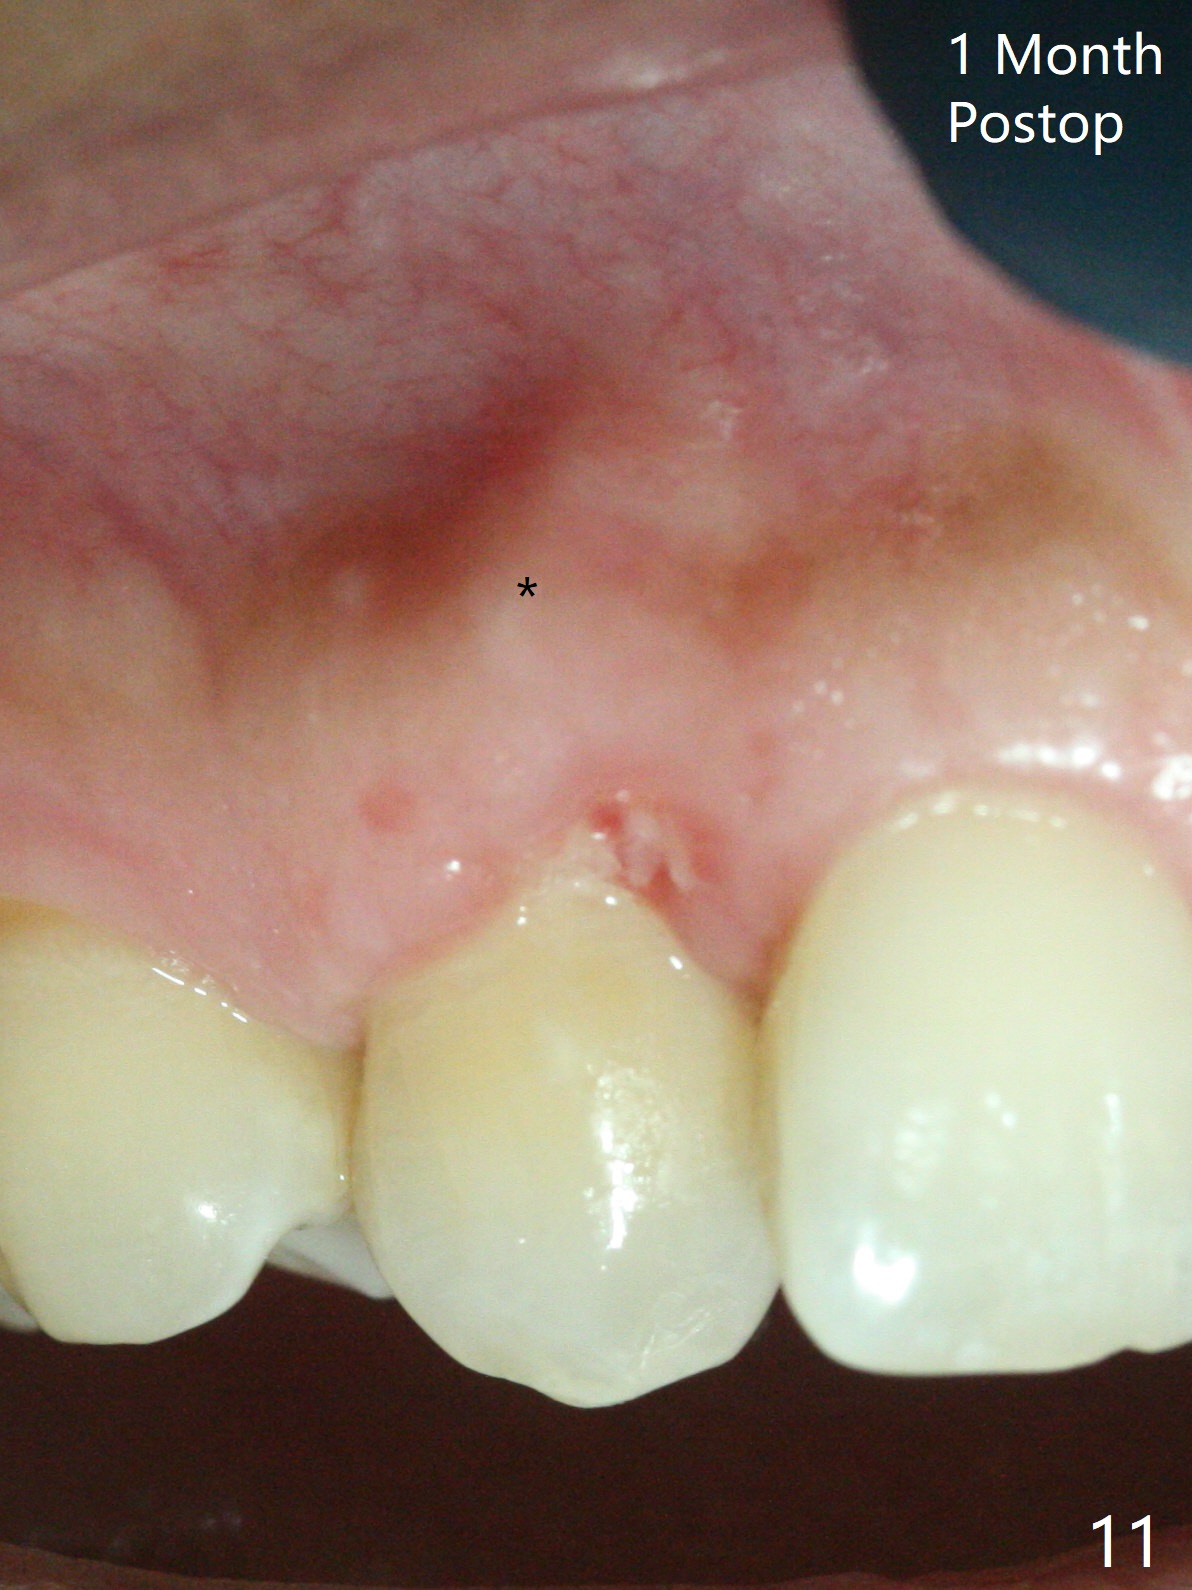

A 54-year-old woman seeks treatment for the tender upper right lateral incisor (Fig.1-4: 2 because of palatal cervical caries (Fig.3 <) and periapical radiolucency (*)), which overlaps with the palatal canine (3). One of treatment options is to extract the lateral and to orthodontically move the canine to the position of the lateral, particularly the root (Fig.5 arrow). When the lateral is removed, the labial bone of the canine is thin (Fig.6). Allograft is placed (Fig.8 * and dashed line), covered with Amnion-Chorion Allograft (Bioxclude) and sutured with 4-0 PGA (Fig.7). The wound heals 9 days postop (Fig.9,10). The patient is grateful because of no pain, which she thinks is due to bone graft, whereas Amnion-Chorion membrane is another contributory factor. The lateral root convexity remains 1 month postop (Fig.11 *); she is undecided upon orthodontic treatment.